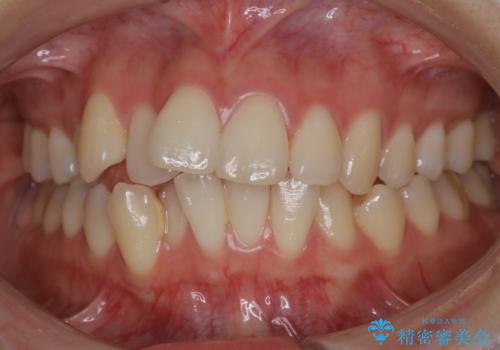

非抜歯でも劇的変化 インビザライン矯正治療

- 前歯のガタつきと噛み合わせの改善を主訴に初診来院され、審査の結果マウスピース装置による非抜歯での矯正を行うこととなりました。

元々の顎骨や口腔・歯槽骨が小さく、どうしても歯が並びきらない状況になっていました。マイクロインプラントという固定源からゴムかけを行うなど、補助装置を活用しながら臼歯部を順番に遠心方向(奥)に移動させていくことで抜歯をしなくても歯が並ぶよう計画を立てました。

歯のガタつきを治すため矯正治療を希望。審査の結果、非抜歯での矯正が可能であるという見通しが立ったためインビザラインによる非抜歯矯正治療を行った。